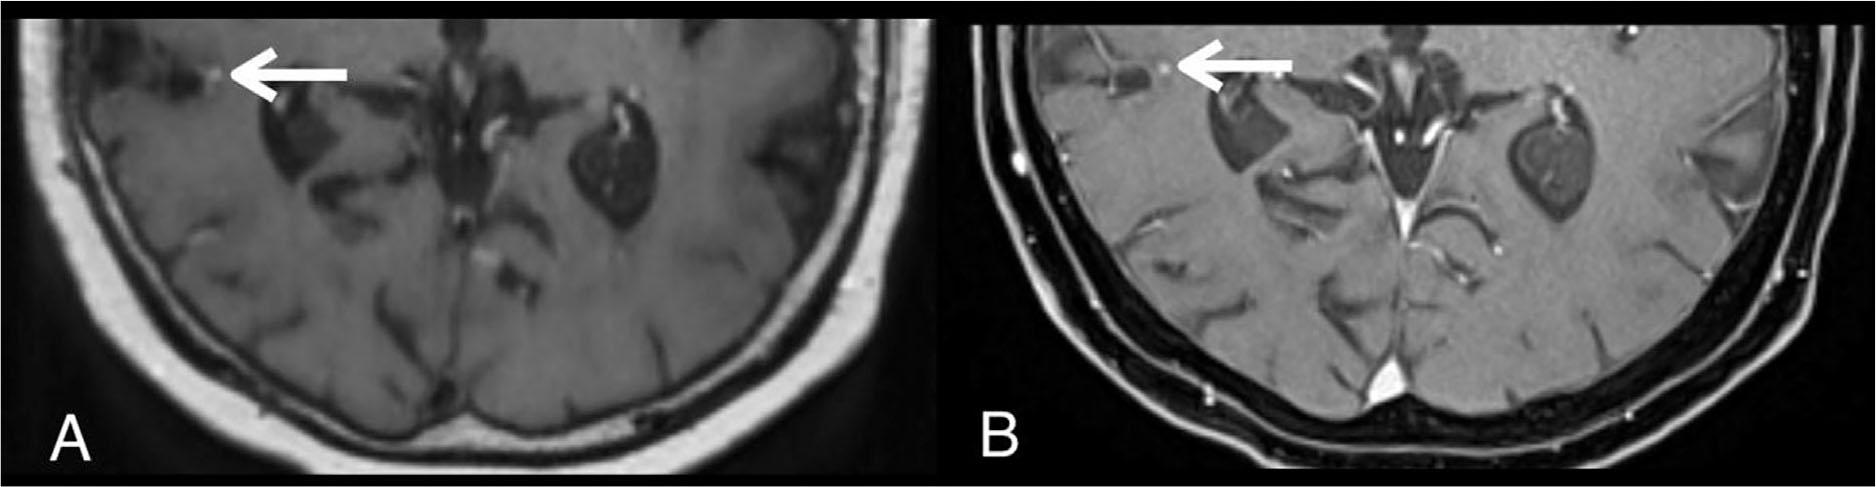

Figure 2

A 76-year-old lung cancer patient with a brain metastasis in the right temporal lobe (white arrow) that was missed by readers on contrast-enhanced 3D T1-weighted SPACE. Axial contrast-enhanced 3D T1-weighted SPACE (A) and contrast-enhanced 3D T1-weighted VIBE (B). The degree of enhancement is similar on both sequences. However, this lesion was missed because it located close to a vessel and was mistaken for an incompletely suppressed vascular signal on contrast-enhanced 3D T1-weighted SPACE (A). Axial contrast-enhanced 3D T1-weighted VIBE (B) clearly distinguishes parenchymal enhancing lesion and adjacent vascular structure.

Another different characteristic between spin-echo-based sequences and gradient-echo-based sequences is the signal intensity of the flowing blood [7]. The signal intensity of the flowing blood in SPACE and other spin-echo-based sequences is black (i.e., signal void), while the signal intensity of the flowing blood in MPRAGE and VIBE which are gradient-echo sequences is white (i.e., flow-related enhancement). The high signal intensity in the blood vessels may confuse the reader and obscure the high signal intensity in enhancing lesions. We believed that the distinct characteristics of the SPACE and VIBE sequences have partly induced the discrepancy in the number of detectable lesions in the first-level analysis. This study found that some of the discrepancies in the number of the detectable parenchymal enhancing lesions on each sequence during the separate readings were due to human error. Those lesions were missed on the separate reading but were visible on both sequences on head-to-head analysis. The source of the discrepancies occurred because the enhancing lesions were less conspicuous, looked like a vascular structure, located near a vascular structure, or had a very tiny size (Figures 1 and 2). The obscured lesions due to susceptibility signal loss were not observed in this study.

Similar with previous studies [23, 26], this study found one false-positive lesion on the SPACE due to the scattering regions of short-segment vascular enhancement (Figure 7). On SPACE sequence alone, it is difficult to differentiate the enhancing metastasis from the partial hyperintensity in slow flow blood vessel when the continuity with the adjacent tubular-shaped vascular structure is lost. A study has suggested that concurrent review of 3D T1-weighted gradient-echo-based sequence (e.g., MPRAGE or VIBE) and 3D T1-weighted fast spin-echo-based sequence (e.g., SPACE) was helpful for differentiating the nature of the enhancing foci by showing their continuity with vascular structures [26]. We confirmed that the rest of the enhancing lesions detected on SPACE sequence were not false-positive lesions by head-to-head comparison of the lesions on both VIBE and SPACE sequences. Some investigators proposed additional options such as motion-sensitized magnetization prepared pulse and its variants to improve vascular signal suppression at the expense of higher susceptibility to motion due to longer acquisition time [30, 31, 32].